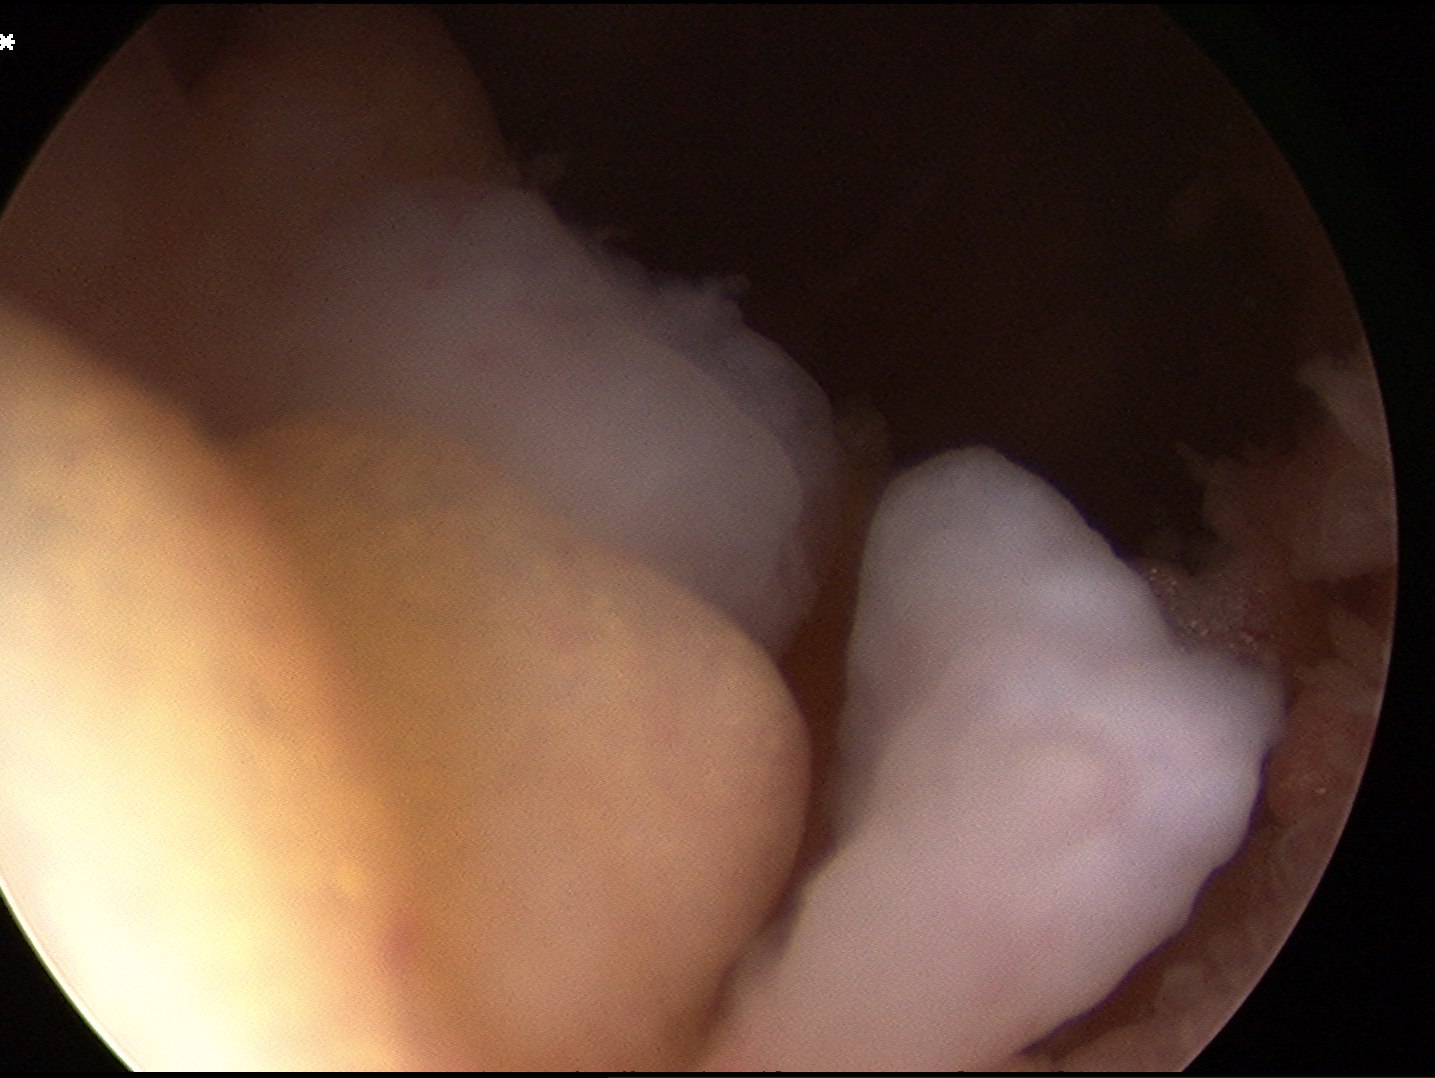

Arthroscopy

Synovial proliferation

- localised or generalised

- can see cartilage growing from synovium

Multiple loose bodies +++